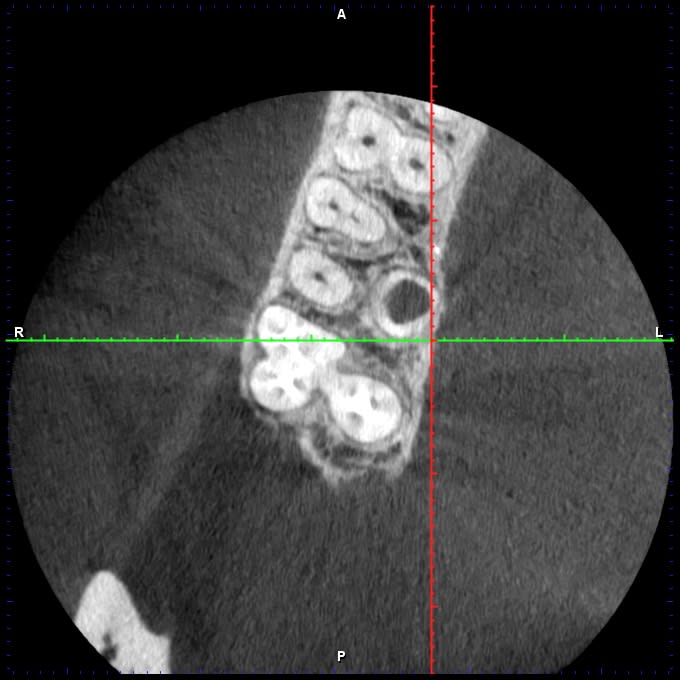

J'ai ce matin un patient qui se présente pour une fracture de 16, asymptomatique.

Test froid négatif, la dent présente une PDP qui radiologiquement ressemble à de la biodentine, cliniquement parait plus blanc.

Je fait une cbct: 4 canaux, lésion infectieuse sur chaque racine et surtout, ce qui ressemble à une résorption interne de la racine palatine.